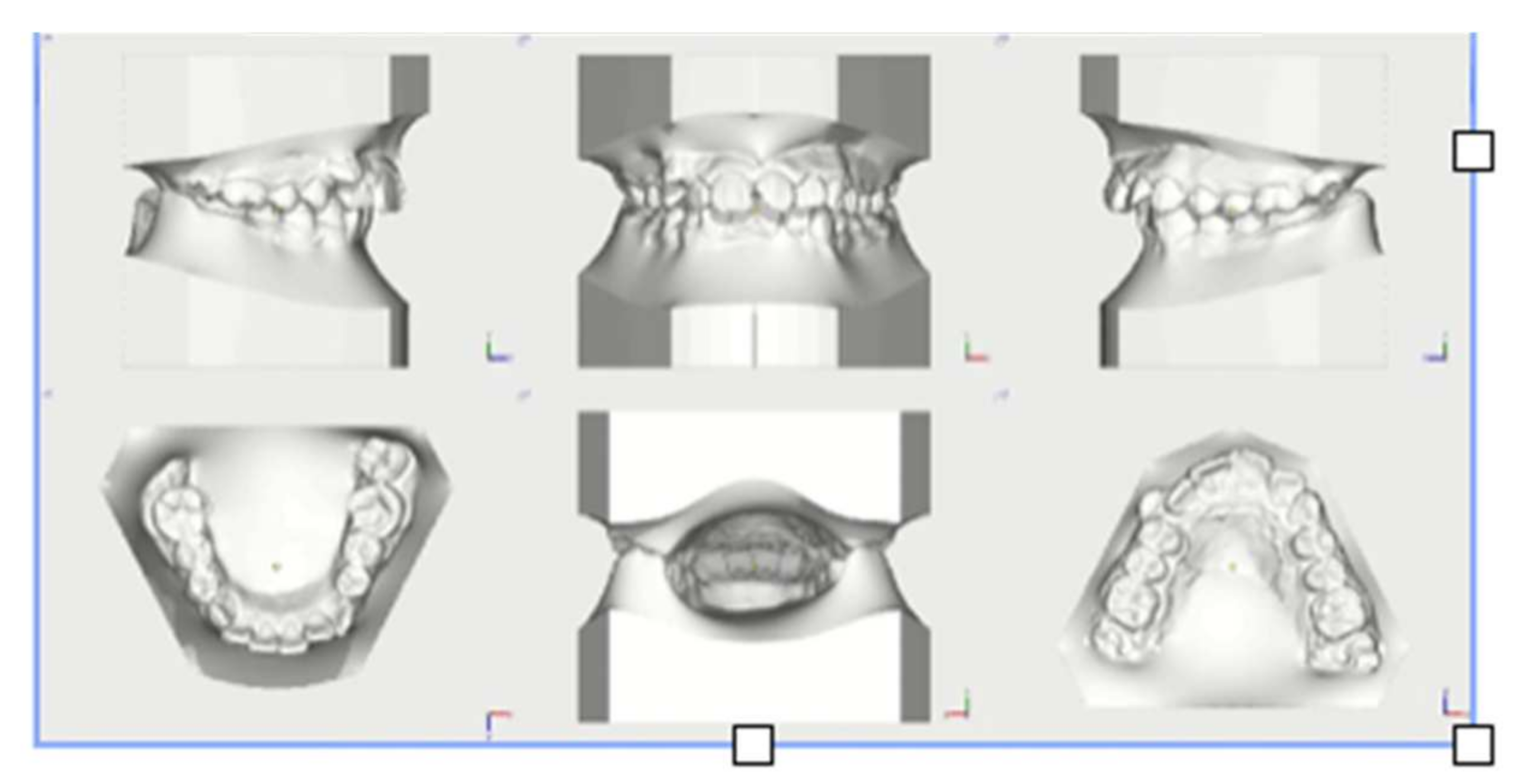

2. Diagnosis and Etiology

5. Treatment Progress

6. Treatment Results